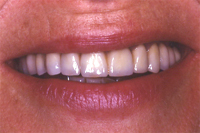

Ein seitlicher Oberkieferschneidezahn ist als sogenannter Zapfenzahn (angeboren) in die Mundhöhle durchgebrochen (Abb. 1). Nach orthodontischer Zahnbehandlung haben wir dem 16 Jahre alten Mädchen den Vorschlag gemacht, mittels zwei adhäsiv gelegten Kompositfüllungen und ohne Beschleifen den Zapfenzahn in einen natürlichen Schneidezahn umzuformen (Abb. 2).